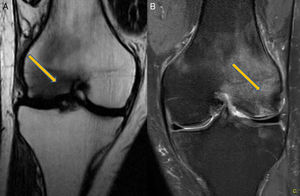

Clinical CaseA 41 year old male with no medical history of interest, presented at the surgery with right knee pain and minimum trauma. Diffuse bone marrow oedema involving the external condyle was reported. Four months later he presented with bone marrow oedema in the ipsilateral internal condyle (Fig. 1). In other magnetic resonance images we found new bone marrow oedema extension, in the internal femoral condyle of the contraleteral knee and later in the external condyle and pain in the right knee, the NMI of which also showed bone marrow oedema (Figs. 2 and 3). Treatment with NSAIDS was administered and partial load-bearing but this was ineffective.

In the differential diagnosis its distinction is interesting, compared with the algodystrophy of Südeck, reflex sympathetic dystrophy or complex regional pain syndrome. This condition is painful after a traumatic event, sometimes with low intensity, and presents with allodynia (or intense pain on response to non painful stimuli), hyperalgesia, and vasomotor disorders with vegetative symptoms. In transient migratory osteoporosis these vegetative symptoms do not arise. Furthermore, the marrow bone oedema presents as an imaging pattern in the NMI characterised by low-intensity signals in T1 and high-intensity signals in STIR T2 in bone marrow. When this oedema appears in several joints without osteonecrosis images, and not in any isolated form, we would diagnose a transient migratory osteoporosis.